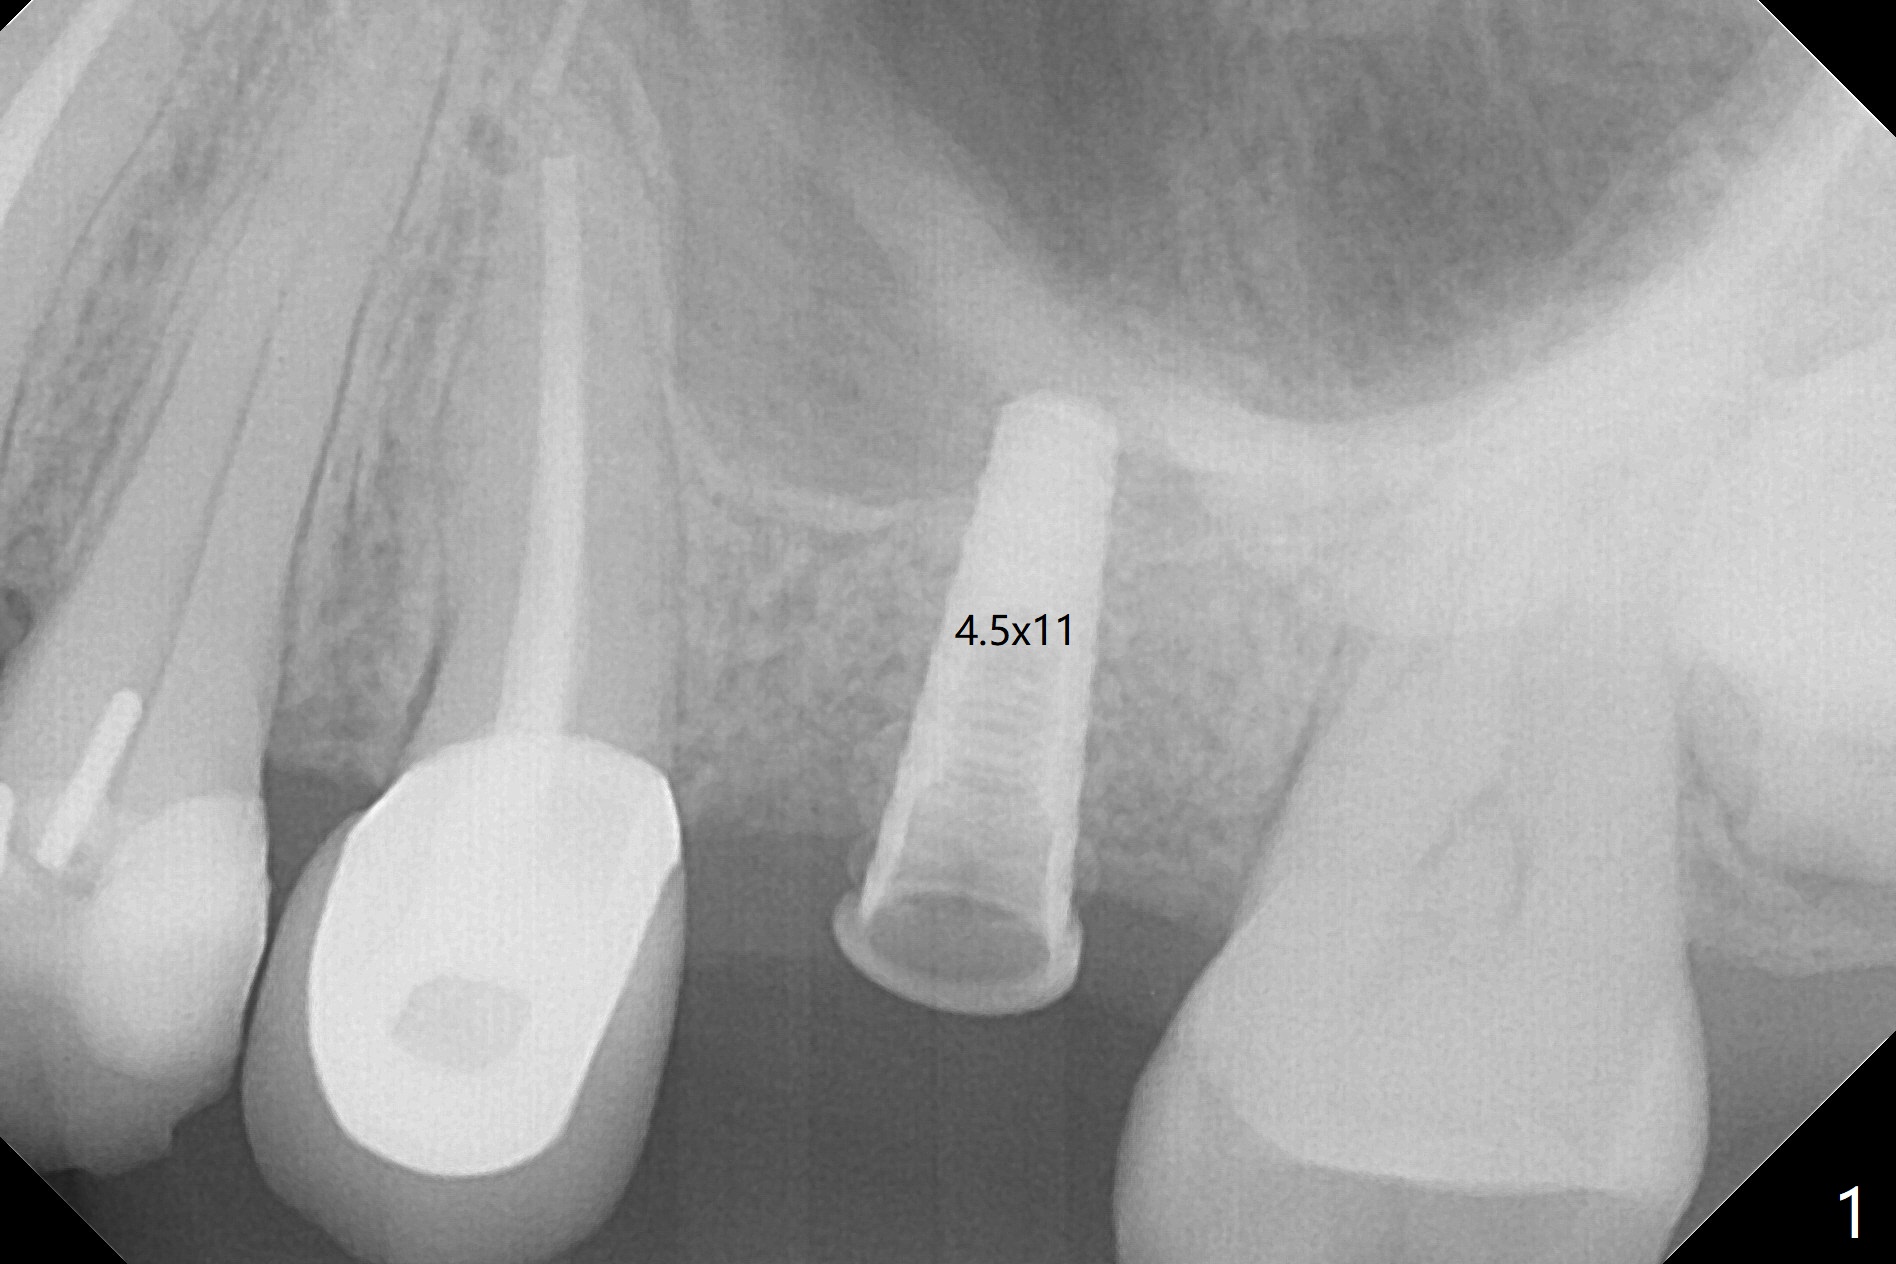

The ridge is wide at #14 11 months post socket preservation. Access and bone expansion (BEB) starts with Magic Split, followed by Magic Expanders 3.0, 3.8 and 4.3 mm from 8 to 9 mm for sinus lift. No bone is removed for osteotomy. Instead bone condensation occurs. After placement of a 4.5x11 mm dummy FC implant (Fig.1 with sinus lift (without bone graft)), a 5x9(2) mm Magicore (2 mm cuff) is placed with >55 Ncm with cuff margin at the gingival margin (Fig.2); a 5.5x3 mm solid abutment tries in. There is no occlusal clearance; trimming of the solid abutment will be needed. Later a healing screw is placed (Fig.3 *). There is no bone loss 5.5 months postop (Fig.4). A healing cap is placed without much tissue blanching. Instead a 5.5x3 mm solid abutment is placed; after height adjustment, impression is taken. A permanent crown is temporarily cemented 6 months postop (to rule out food impaction) and permanently re-cemented 7 months postop (Fig.5,6). CBCT taken 3-4 months post cementation shows that the implant threads are within the bone (Fig.7) and that the implant barely enters the sinus (Fig.8 *). That is significant since the patient has chronic sinusitis with thickened sinus membrane (Fig.9 *). The tooth #18 seems to have crazing line 10 months post cementation of the crown at #14 (overloading, Fig.10).